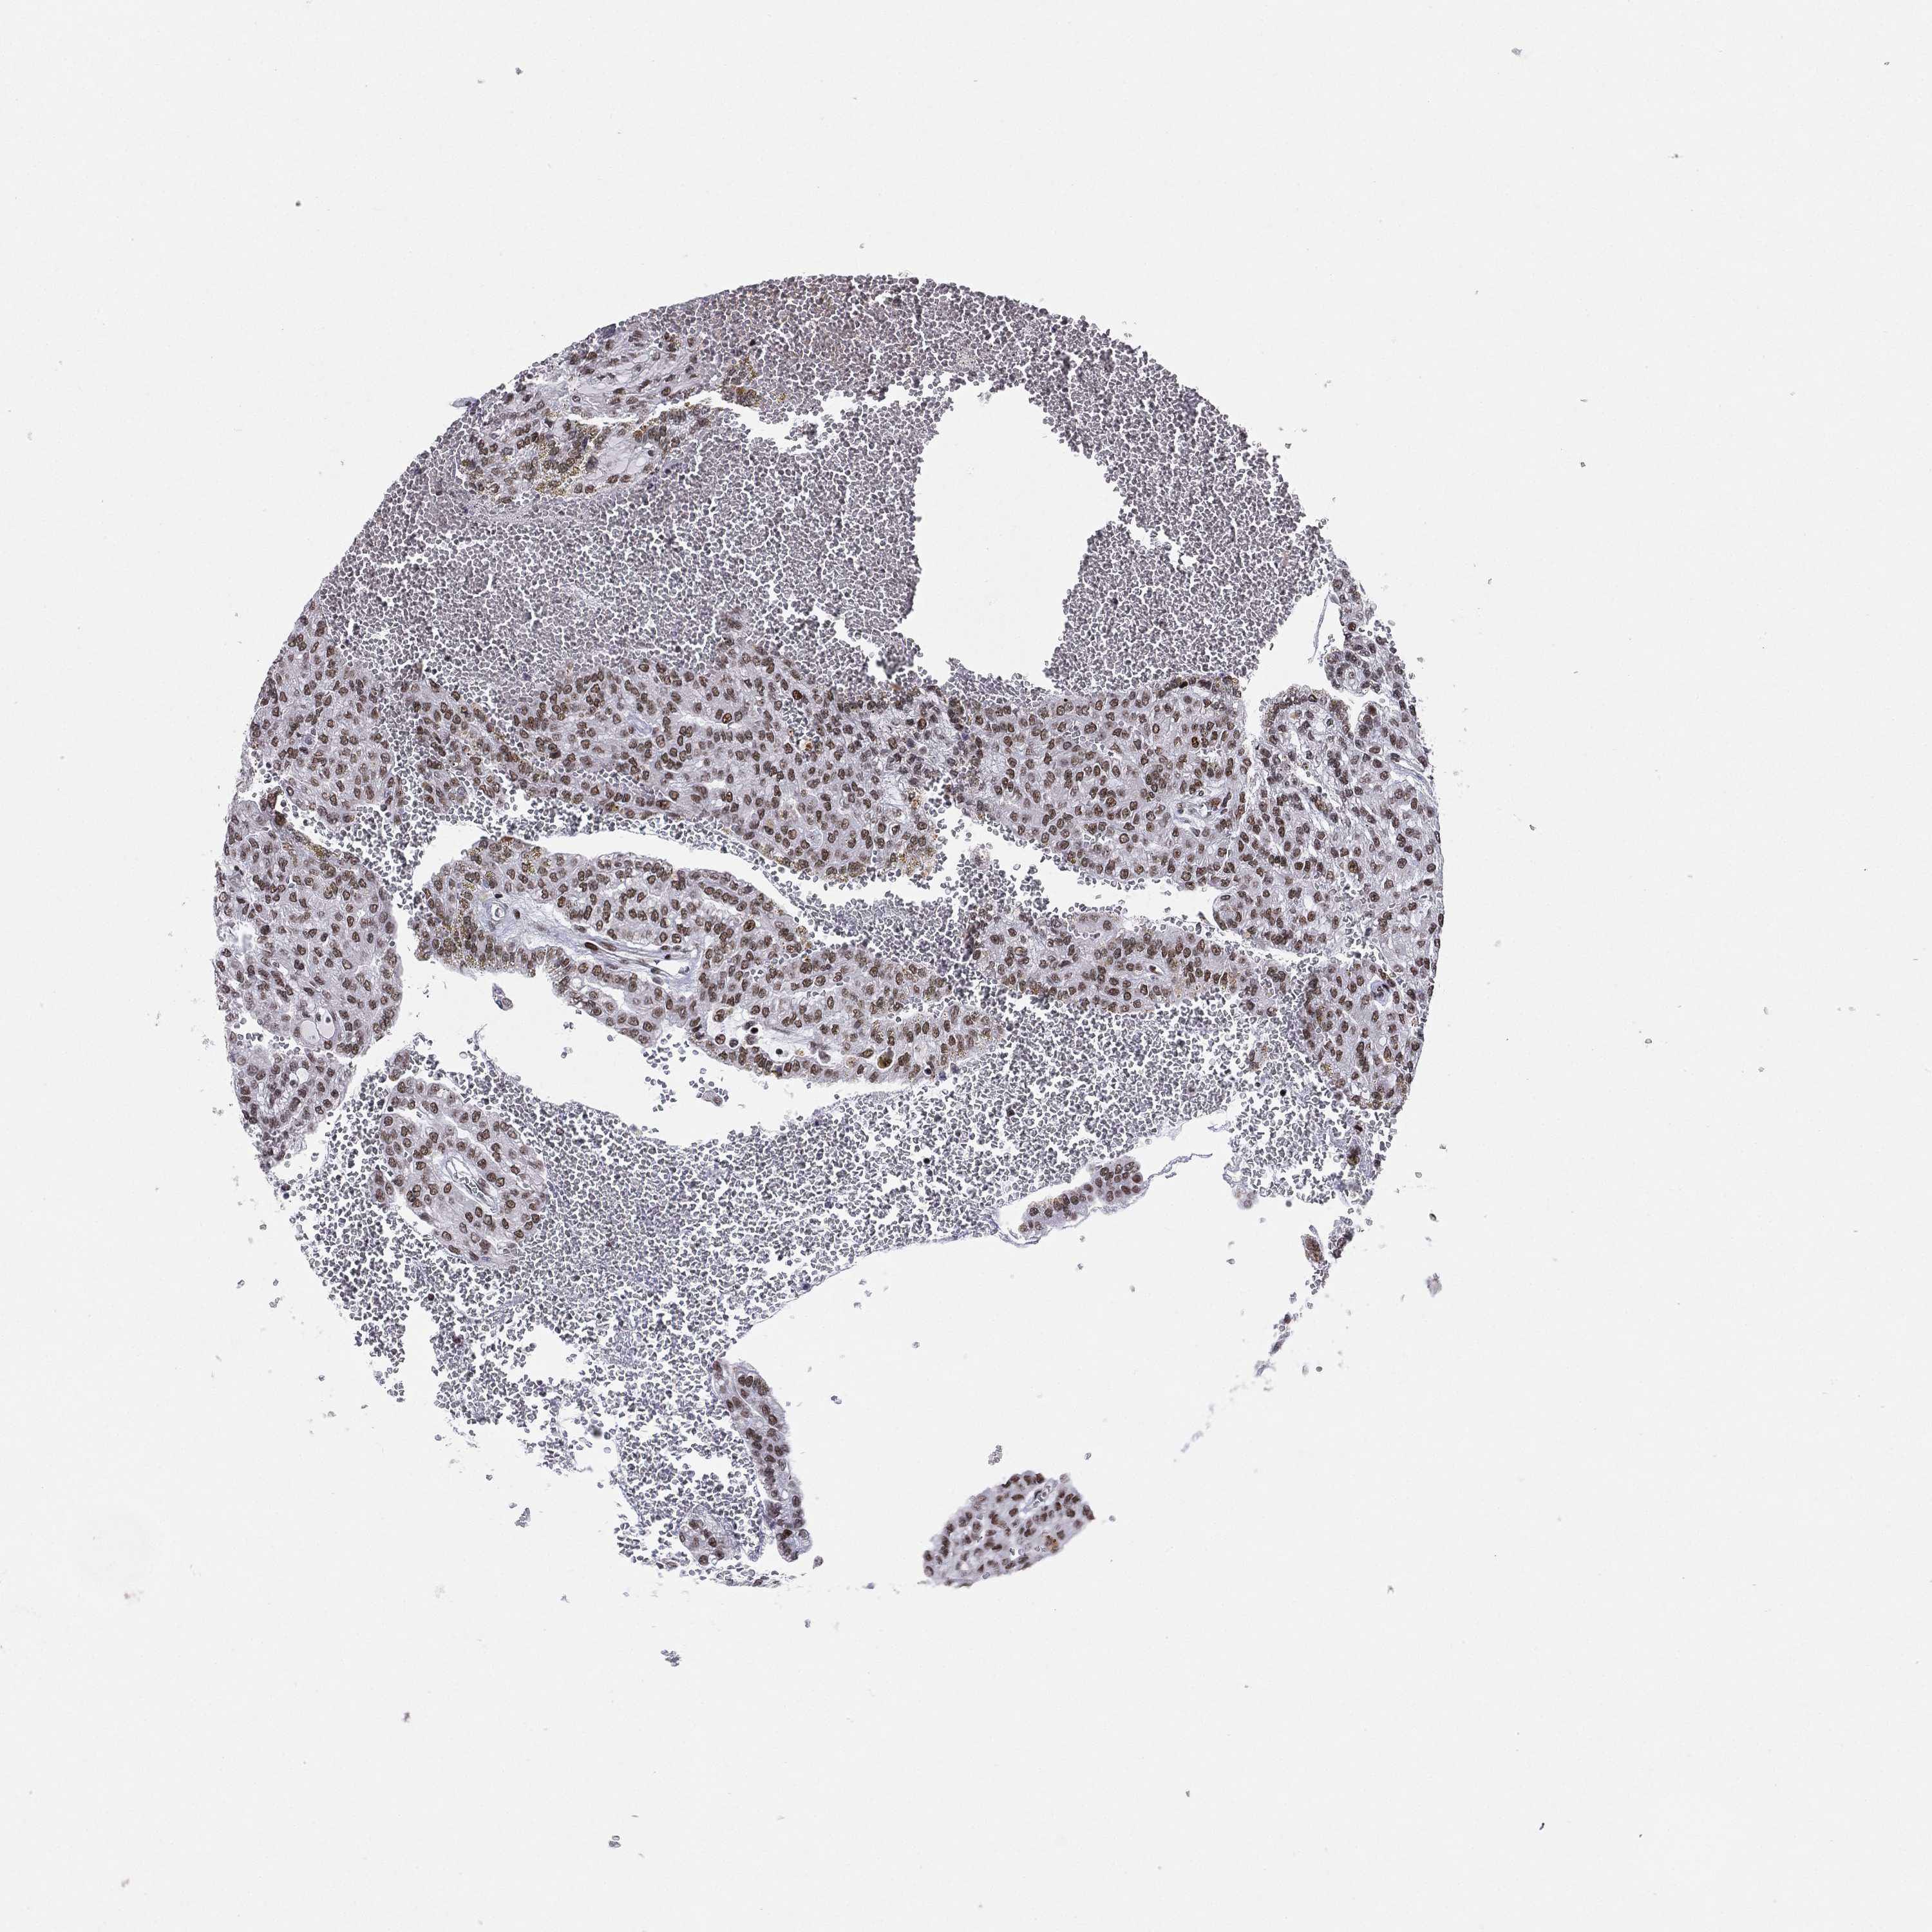

KIDNEY CHROMOPHOBE (TCGA) - Interactive survival scatter ploti

The Survival Scatter plot shows the clinical status (i.e. dead or alive) for all individuals in the patient cohort, based on the same data that underlies the corresponding Kaplan-Meier plots. Patients that are alive at last time for follow-up are shown in blue and patients who have died during the study are shown in red.

The x-axis shows the expression levels (FPKM) of the investigated gene in the tumor tissue at the time of diagnosis. The y-axis shows the follow-up time after diagnosis (years). Both axes are complimented with kernel density curves demonstrating the data density over the axes. The top density plot shows the expression levels (FPKM) distribution among dead (red) and alive patients (blue). The right density plot shows the data density of the survived years of dead patients with high and low expression levels respectively, stratified using the cutoff indicated by the vertical dashed line through the Survival Scatter plot. This cutoff is automatically defined based on the FPKM cutoff that minimizes the p-score. The cutoff can be changed by dragging the vertical line or by entering a cutoff value in the square labeled "Current cut-off".

Under the Survival Scatter plot the p-score landscape (black curve; left axis) is shown together with dead median separation (red curve; right axis). Dead median separation is the difference in median mRNA expression between patients who have died with high and low expression, respectively. It is calculated as follows: median FPKM expression of dead patients with high expression - median FPKM expression of dead patients with low expression. This is intended to aid the user in visually exploring custom cutoffs and the associated p-scores and dead median separation.

Individual patient data is displayed and can be filtered by clicking on one or more of the category buttons on the top of the page. Categories describing expression level and patient information include: high, low, alive, dead, female, male and tumor stages. The scale of the x-axis can be toggled between linear and log-scale by clicking on the "x log" button. Mouse-over function shows TCGA ID, patient information and mRNA expression (FPKM) for each patient.

& Survival analysisi

Kaplan-Meier plots summarize results from analysis of correlation between mRNA expression level and patient survival. Patients were divided based on level of expression into one of the two groups "low" (under cut off) or "high" (over cut off). X-axis shows time for survival (years) and y-axis shows the probability of survival, where 1.0 corresponds to 100 percent.

RTF1 is potential prognostic, high expression is unfavorable in Kidney Chromophobe (TCGA)

Best expression cut offi

Based on the FPKM value of each gene, patients were classified into two groups and association between prognosis (survival) and gene expression (FPKM) was examined. The best expression cut-off refers the FPKM value that yields maximal difference with regard to survival between the two groups at the lowest log-rank P-value. Best expression cut-off was selected based on survival analysis .

When clicking on this number, the vertical dashed line indicating cut-off, the interactive survival plot, and the Kaplan-Meier curve will be adjusted to show results based on the best expression cut-off.

: 21.51

Median expressioni

Median expression refers to the median FPKM value calculated based on the gene expression (FPKM) data from all patients in this dataset. When clicking on this number, the vertical dashed line indicating cut-off, the interactive survival plot, and the Kaplan-Meier curve will be adjusted to show results based on the median expression.

: N/A

Median follow up timei

Median follow up time refers to the median time (years) after diagnosis with this type of cancer, based on clinical data from all patients in this dataset.

P scorei

Log-rank P value for Kaplan-Meier plot showing results from analysis of correlation between mRNA expression level and patient survival.

N/A

5-year survival highi

5-year survival for patients with higher expression than the expression cutoff.

For melanoma and glioma, 3-year survival is shown.

5-year survival lowi

5-year survival for patients with lower expression than the expression cutoff.

TCGA RNA samplesi

RNA-seq data is reported as average FPKM (number Fragments Per Kilobase of exon per Million reads), generated by the The Cancer Genome Atlas (TCGA) .

Normal distribution across the dataset is visualized with box plots, shown as median and 25th and 75th percentiles. Points are displayed as outliers if they are above or below 1.5 times the interquartile range. FPKM values of the individual samples are presented next to the box plot.

Average pTPM 20.0

Number of samples 64